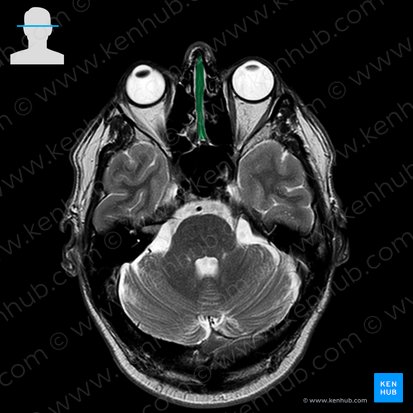

Die Nasenscheidewand, auch Nasenseptum genannt, ist die vertikale Trennwand in der Mitte der Nasenhöhle, die sie in eine linke und eine rechte Hälfte trennt. Sie besteht aus einem hinteren knöchernen und einem vorderen knorpeligen Abschnitt.

Der knöcherne Teil des Septums besteht aus zwei Knochen: der Lamina perpendicularis des Siebbeins (Os ethmoidale) oben und dem Pflugscharbein (Vomer) unten. Das Vomer artikuliert mit seinem oberen Rand am hinteren Ende mit der Lamina perpendicularis des Siebbeins. Diese geht nach oben in die Lamina cribrosa über.

Zwischen den beiden Knochen des Septums befindet sich vorne eine Lücke, die von einer Knorpelschicht, dem sogenannten Septumknorpel, ausgefüllt wird. Der Septumknorpel besteht aus hyalinem Knorpel und bildet den nicht verknöcherten Teil der senkrechten Platte des Siebbeins, der sich recht weit nach hinten zwischen den beiden Knochen erstrecken kann.

Struktur Knöcherner Anteil: Pflugscharbein (Vomer) und Lamina perpendicularis des Siebbeins (Os ethmoidale)

Knorpeliger Anteil: Cartilago septi nasi